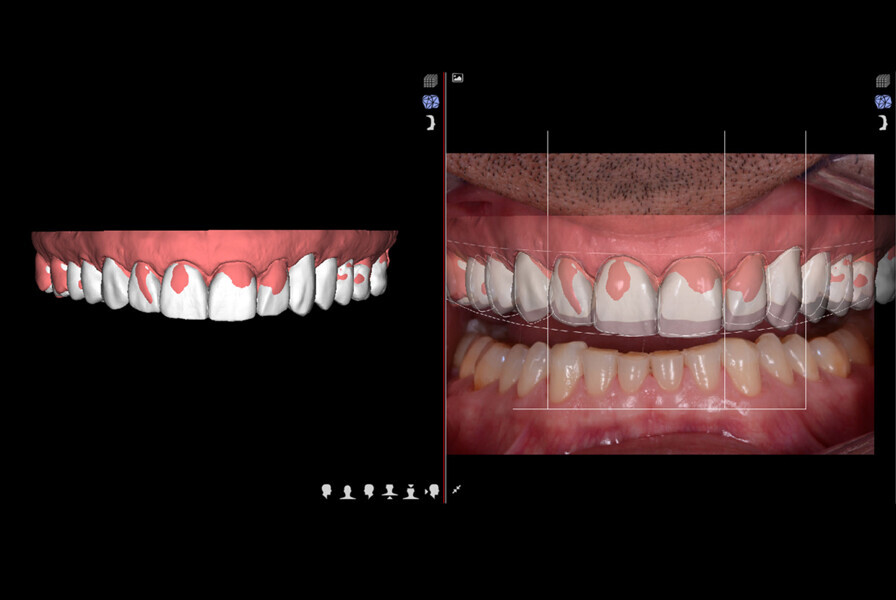

Fig. 10: Final veneers and crowns digitally prepared using the Ceramill Mind design software and produced in a milling machine (Ceramill

Motion 2) from machinable lithium disilicate ceramic blocks (VITABLOCS TriLuxe forte).